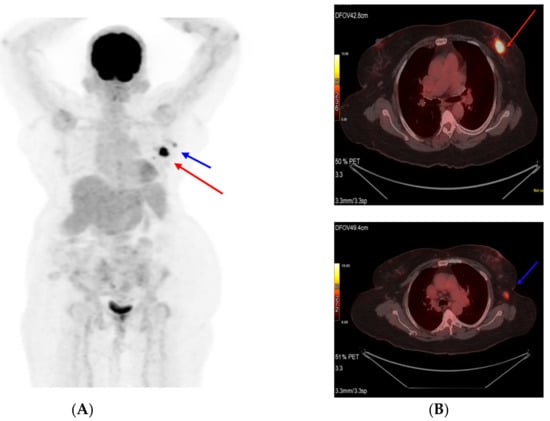

Figure 3.

PET scan images at interim assessment after six cycles of T-DM1 (A). Primary tumor (target 1) shown as a red arrow and (B) axillary lymph node (target 2) shown as a blue arrow.

A response evaluation via a PET CT scan showed a significant decrease in the size and metabolic activity of the primary left breast lesion, along with regression and metabolic resolution of the left level-I axillary nodes in the patient (partial response, PR, by RECIST 1.1). The patient underwent surgery, namely modified radical mastectomy. A post-operative histopathological examination was suggestive of residual disease with invasive ductal carcinoma, grade: II, tumor size: 1.2 cm, lymph nodes: 1/25, and ypT1cN1aMx. In view of pathological complete response not being achieved, it was decided to continue T-DM1 and complete one year of anti-HER2 therapy. The patient completed one year of T-DM1 therapy with no adverse events. A PET CT scan was performed in May 2022 and showed no evidence of metabolically active disease (Figure 4). She had completed twelve total cycles of T-DM1 and opted to continue with endocrine therapy. She was subsequently initiated on endocrine therapy and continued dialysis. In order to publish this report, written informed consent was obtained from the patient and her legal guardian for the disclosure of images and clinical details.